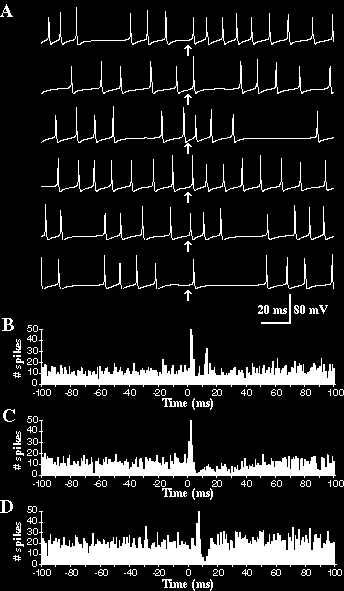

Zapis aktywności pojedynczych neuronów pokazuje potencjały czynnościowe, ale wymaga wprowadzenia elektrod do mózgu, co jest procedurą inwazyjną.

Można ją stosować w badaniach na zwierzętach, lub w przypadku poważnych chorób mózgu u ludzi.

mierząca lokalne potencjały sensorami bezpośrednio na powierzchni mózgu. Jest to jednak metoda inwazyjna. Bezpośrednie pomiary aktywności pojedynczych neuronów stosuje się głównie w badaniach nad zwierzętami, lub rzadko w przypadku padaczki u ludzi.